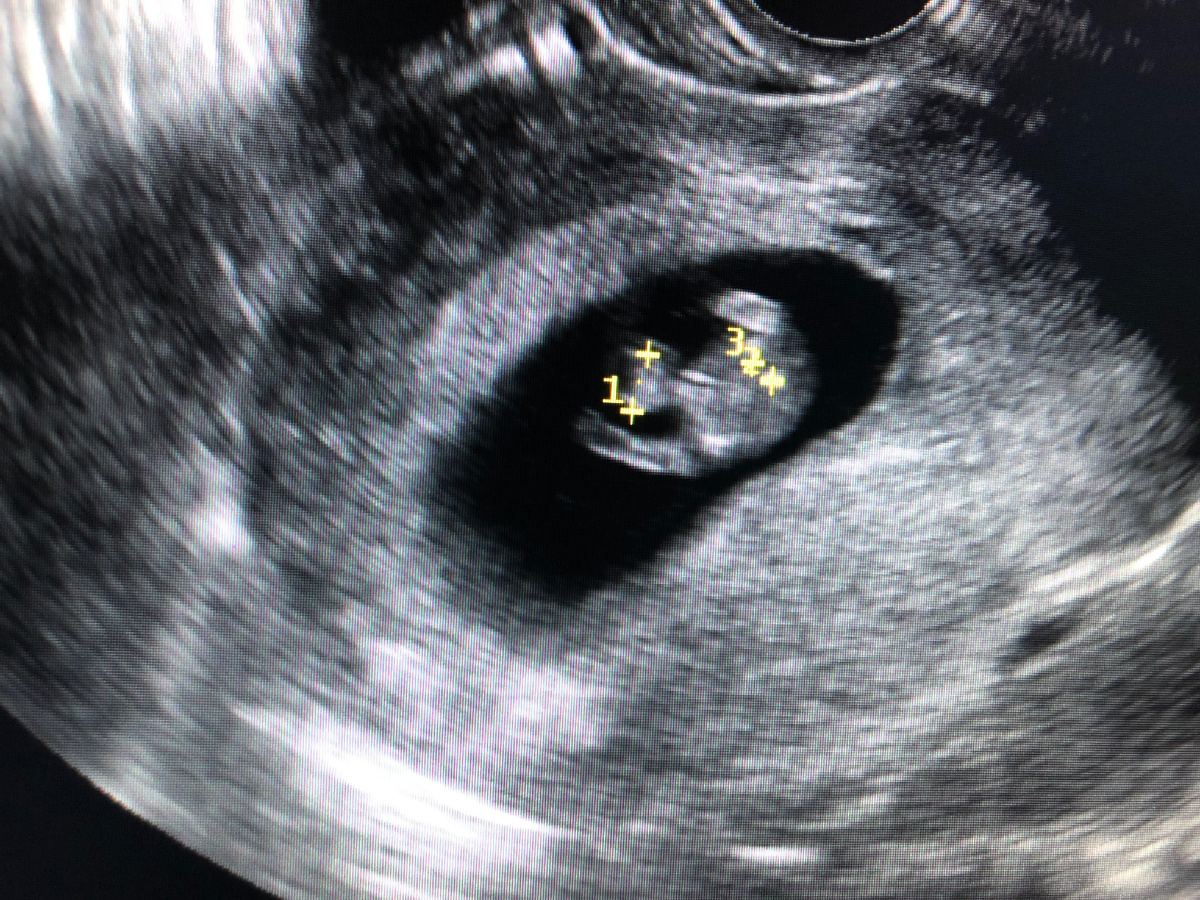

По УЗИ в стационаре обнаруживается ретрохориальная гематома. Эмбрион не нашли. Ставят начавшийся выкидыш. Нужно выскабливать. Врачи черствые, врачам все равно.

В другом месте специалист находит эмбрион. Сердце бьется, 162 удара в минуту.

Состояние налаживается. Ее выписывают. Контрольное УЗИ, на котором гематомы уже нет.

Снова гематома, но эмбрион живой.